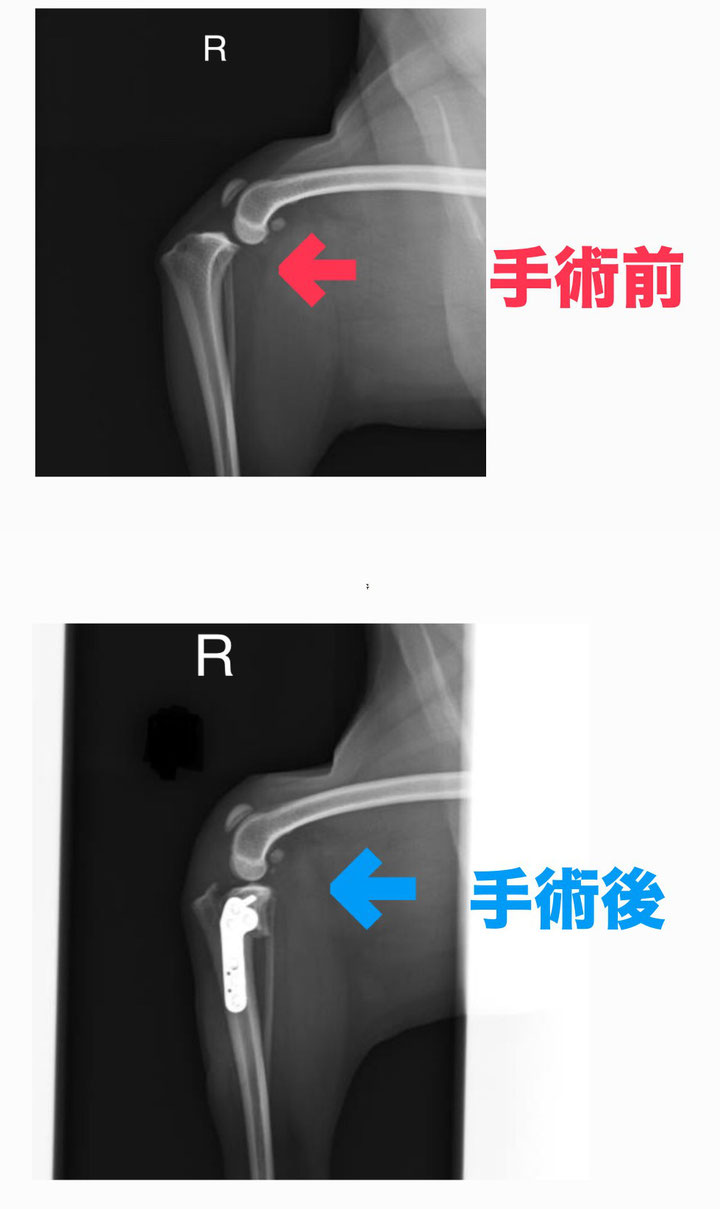

📸 上の画像は、TPLO手術前後のレントゲン写真です。

手術前(赤い矢印):脛骨が前方にずれ、関節が不安定な状態。

手術後(青い矢印):脛骨の角度を調整し、金属プレートで固定することで膝関節が安定しています。

このように、TPLO手術によって関節にかかる力の方向を変え、靱帯の代わりに安定性を保つことができます。